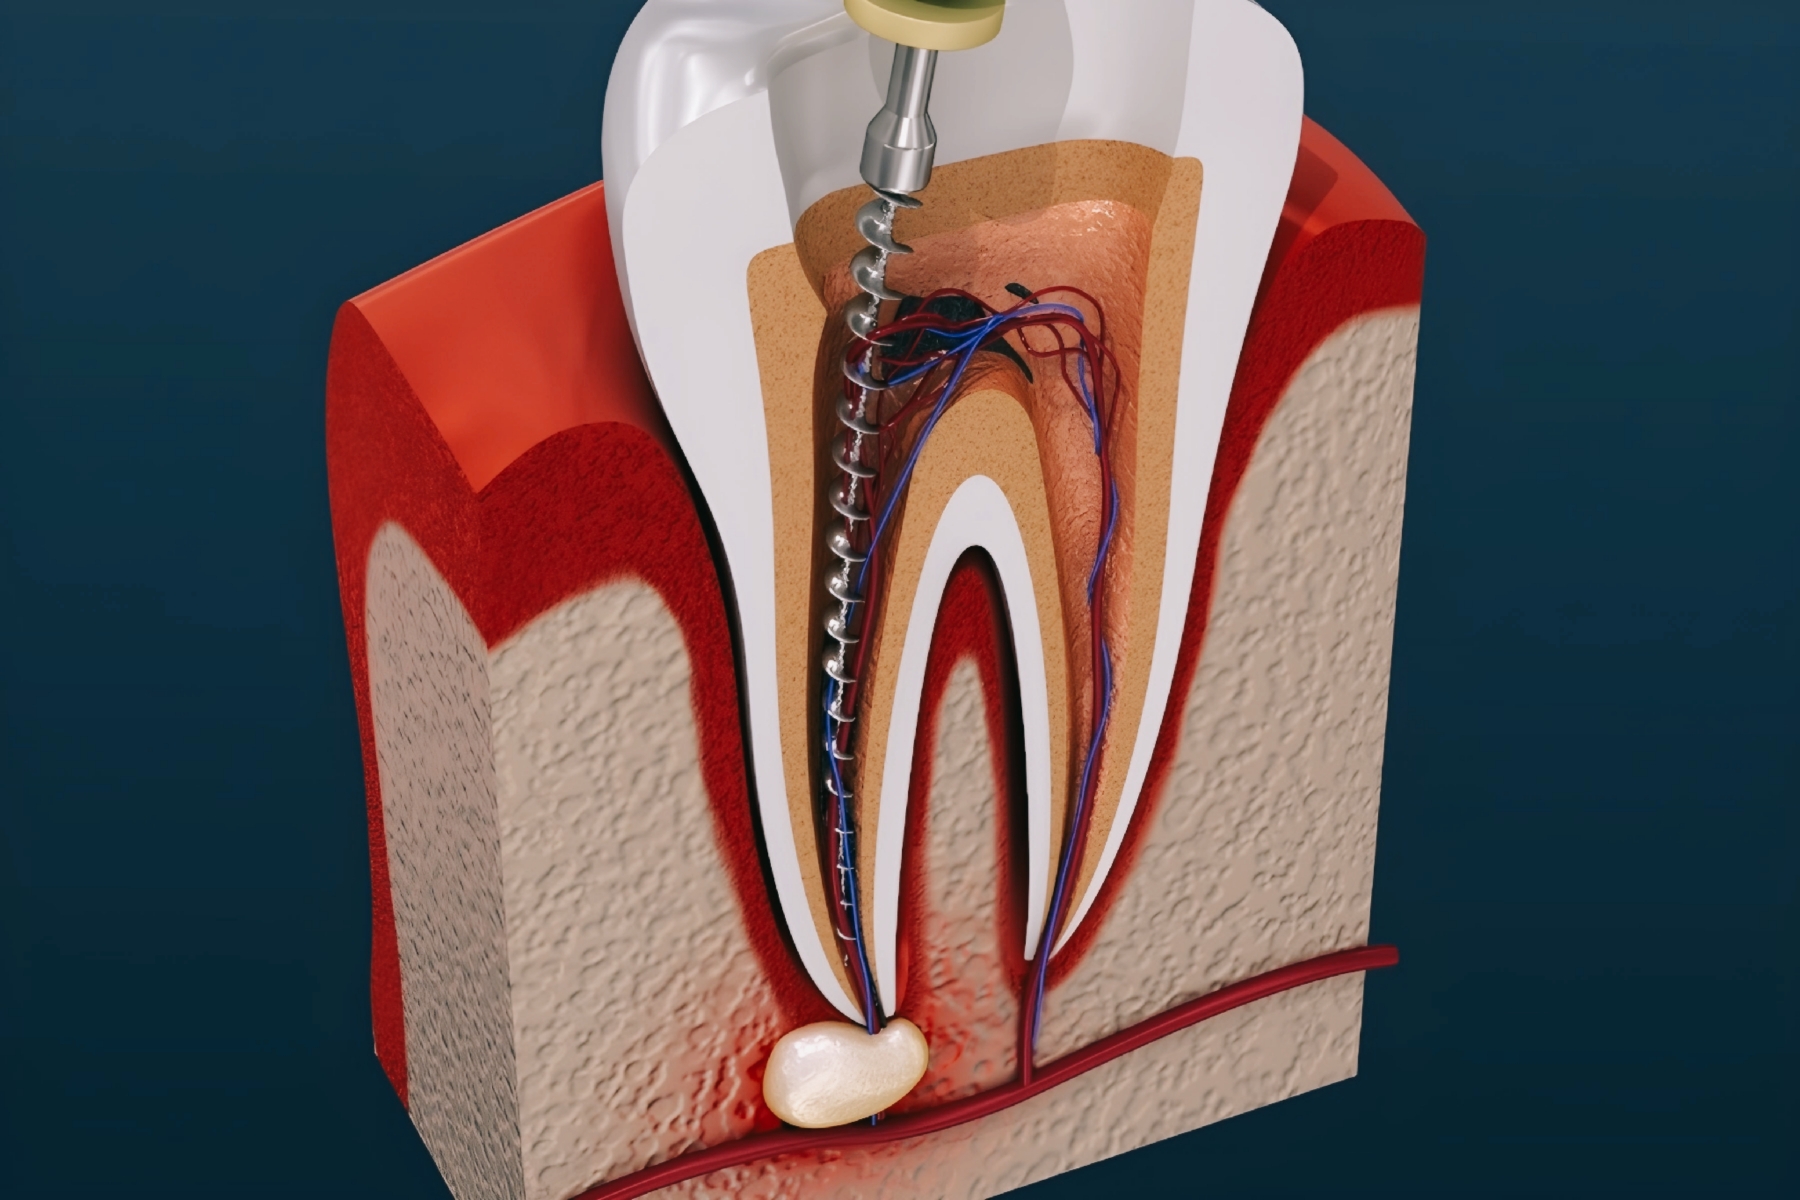

مراحل درمان ریشه دندان یا عصب کشی دندان

در مرحله اول ابتدا، برای انجام معاینه و بررسی وضعیت و میزان آسیب دندان عکس رادیولوژی (عکس opg )از دندان گرفته می شود. به منظور این که درد هنگام انجام درمان ریشه دندان فرد را اذیت نکند، از داروی بی حسی موضعی برای جلوگیری از احساس درد استفاده می شود. البته درد هنگام عصب کشی دندان ممکن است به خاطر آبسه و عفونت دندان بسیار زیاد باشد. بعد از بی حس کردن دندان، میله پلاستیکی برای خارج کردن بزاق دهان، داخل دهان بیمار قرار داده می شود.. سپس پوسیدگی هایی که در دندان ایجاد شده است، برداشته شده و عاج دندان برای دسترسی به ساقه پالپ دندان باز می شود. و از یک ابزار کوچک هم برای خارج کردن عفونت ها استفاده می شود.

2. مرحله دوم درمان ریشه دندان

در مرحله دوم عصب کشی دندان پس از برداشتن پالپ آسیب دیده، ساقه پالپ و کانال های ریشه خالی و تمیز می شوند. این مهم است که قبل از پر کردن دائم کانال های ریشه، تمامی بخش های کانال از تمام عفونت ها پاک شده و خشک شوند. البته این نکته را هم باید بگوییم که هنگام تمیز و خالی کردن کانال های دندان، کانال های ریشه دندان ممکن است تغییر شکل بدهند و بزرگ شوند تا به دسترسی برای پر کردن دندان راحت تر انجام شود. بعد از خالی کردن و تمیز کردن کانال دندان داروهایی به منظور تمیز کردن و خالی کردن دندان ار هرگونه عفونتی داخل کانال دندان ریخته می شود و ممکن است دندان بیمار برای خارج شدن مایع و ترشحات احتمالی از آن برای چند روز باز باقی بماند. اگر عفونت به لایه های داخلی دندان یعنی ریشه دندان نفوذ کرده باشد، ممکن است برای بیمار آنتی بیوتیک تجویز شود. چنانچه درمان ریشه دندان نیازمند چند جلسه درمان باشد، دندان را به صورت موقت پر می کنند تا دندان از مواد غذایی و تماس با بزاق دور نگه داشته شود. در هر صورت در این مدت از جویدن یا گاز گرفتن با استفاده از دندانی که در حال عصب کشی است تا زمانی که دندان درمان شده و ترمیم شود، پرهیز کنید.

3. مرحله سوم درمان ریشه دندان

پس از خالی کردن عفونت ها به صورت کامل و خشک کردن دندان، کانال دندان پر می شود. در این مرحله ممکن است نیاز به تزریق مواد بی حسی باشد. اگر همانطور که در مرحله دوم گفته شد دندان شما به صورت موقتی پر شده باشد، ابتدا این پر کردگی برداشته می شود تا به این ترتیب بتوان به ناحیه داخل دندان دسترسی پیدا کرد. در این مرحله از مواد مخصوص دندان پزشکی برای پر کردن دندان استفاده می شود تا به این ترتیب بتوان از حفاظت کانال های ریشه در برابر بزاق و نفوذ مواد خارجی اطمینان پیدا کرد.